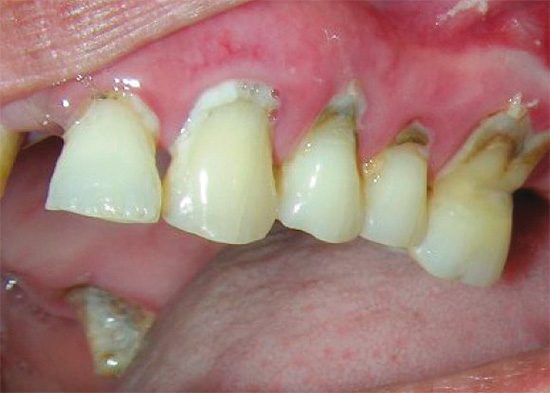

Одной из самых распространенных стоматологических болезней является прикорневой кариес, который поражает зубные ткани у корня, на границе зуба с десной, и даже может выходить за пределы коронковой части. Разрушительный процесс в этой зоне обычно развивается весьма стремительно, поскольку эмаль здесь имеет минимальную толщину: воспаление быстро проникает в глубинные слои зуба, затрагивая корневые каналы.

• потемнение эмали;

• возникновение меловидного пятна с четкими границами;

• образование полости на границе с десной.